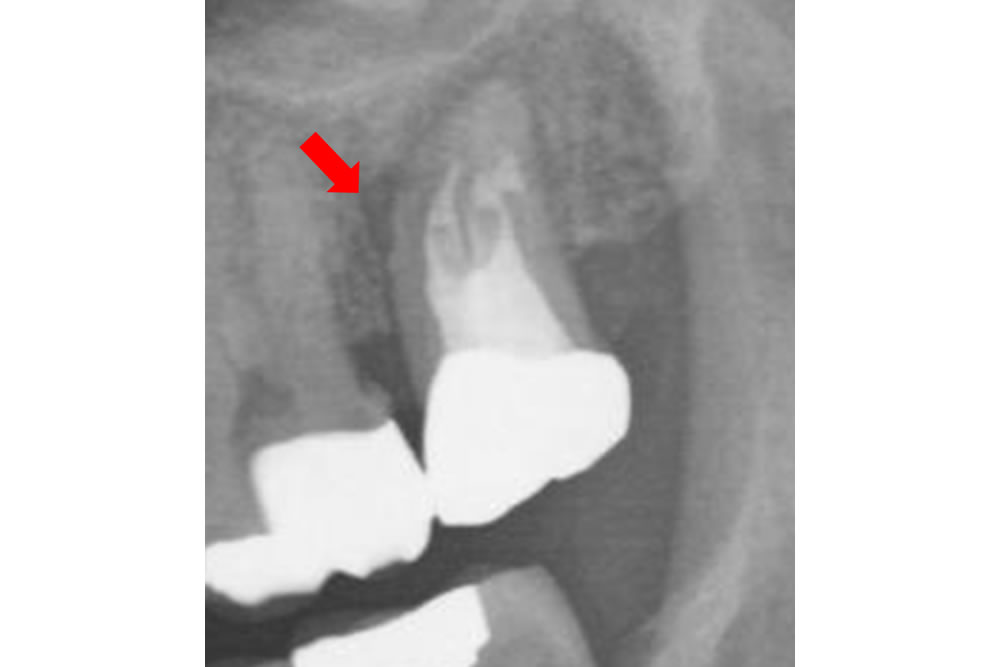

レントゲン画像を診ると、歯根の先に黒い影が広範囲にわたって広がっていました(赤矢印)。また、歯が折れている部分も写っていました(黄矢印)。

そのため、今現在の医学では抜歯と診断するのが原則となっております。

割れ目の部分をさらに拡大して観察すると、溝がかなり深そうです。やはり抜歯が妥当であることは間違いありません。